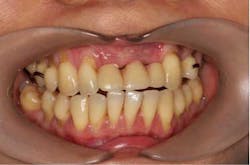

A 43-year-old female with a noncontributory medical history taking no medication and having no known food/drug allergies presented to my general dental office with a chief complaint of having “loose teeth with an underbite.” Clinically, she had generalized, moderate, chronic periodontal disease and was missing teeth Nos. 8 through 10. She had a Class III malocclusion with pathologic flaring of her remaining anterior teeth. She had both vertical and horizontal tissue loss in the No. 8 through 10 region. The patient wore a transitional partial denture to replace the anterior missing teeth that was placed in edge-to-edge occlusion by her previous dentist. (Fig. 1) She did not like having a removable prosthetic and desired a fixed option in the form of implants to replace her missing teeth. I sent her to the periodontist for a periodontal consult for her remaining dentition and dental implants to replace her missing front teeth.

Fig. 2